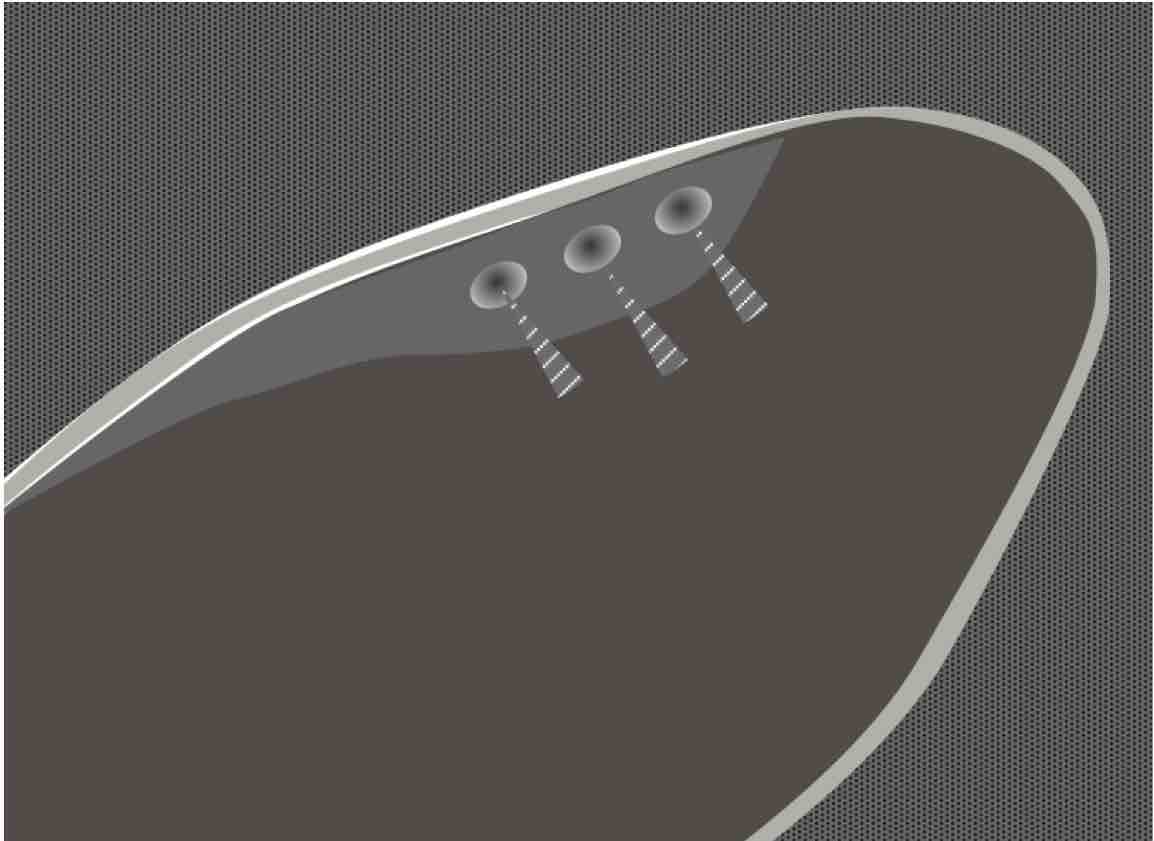

胆嚢腺筋腫症

・胆嚢壁のびまん性あるいは限局性の肥厚で限局型からびまん型まで様々なタイプがある

・胆嚢の粘膜上皮が胆嚢壁の筋肉の層にまで憩室様嵌入したRokitansky-Ashoff洞(RAS)と呼ばれるものが増生したもの

・胆嚢摘出症例の約10%に認められ頻度が高い

・壁内の小嚢胞構造やコメット様エコーを参考にして診断するが、胆嚢腫瘍と鑑別しがたい例もある